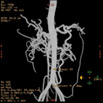

Abd Aorta MIP

显示腹部主动脉及其主要分支血管的起源、走形及其它的形态

Abd Aorta VR

从外形上显示腹部主动脉及其主要分支血管的起源、走形及其它的形态